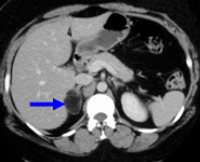

Чаще всего инциденталомы диагностируются в процессе визуализирующих исследований брюшной полости и забрюшинного пространства (УЗИ, КТ, МРТ), выполняемых по поводу других заболеваний.

При выявлении того или иного опухолевого образования надпочечников на следующем этапе уточняется его гормональная активность и гистологическая структура. С этой целью выполняется определение базального уровня гормонов надпочечников (кортизола, альдостерона, эстрогенов, андрогенов, катехоламинов) и их содержания в крови в ответ на стимулирующие пробы. Кроме гормональных тестов, при выявлении инциденталом проводится исследование уровня калия крови (для исключения гиперальдостеронизма), дегидроэпиандростерон сульфата - маркера секреции андрогенов.

В рамках диагностики инциденталом выполняется селективная ангиография (артериография, флебография), доплерография надпочечников, радионуклидная сцинтиграфия, экскреторная урография. Вопрос о тактике лечения при случайных инциденталомах решается по результатам тонкоигольной аспирационной биопсии надпочечника. Несмотря на высокую информативность биопсии, применение ее ограничено в связи с высокой вероятностью развития осложнений (гемоторакса, пневмоторакса, кровотечения, гематурии, гематомы почечной или печеночной паренхимы, панкреатита, инфекции ).